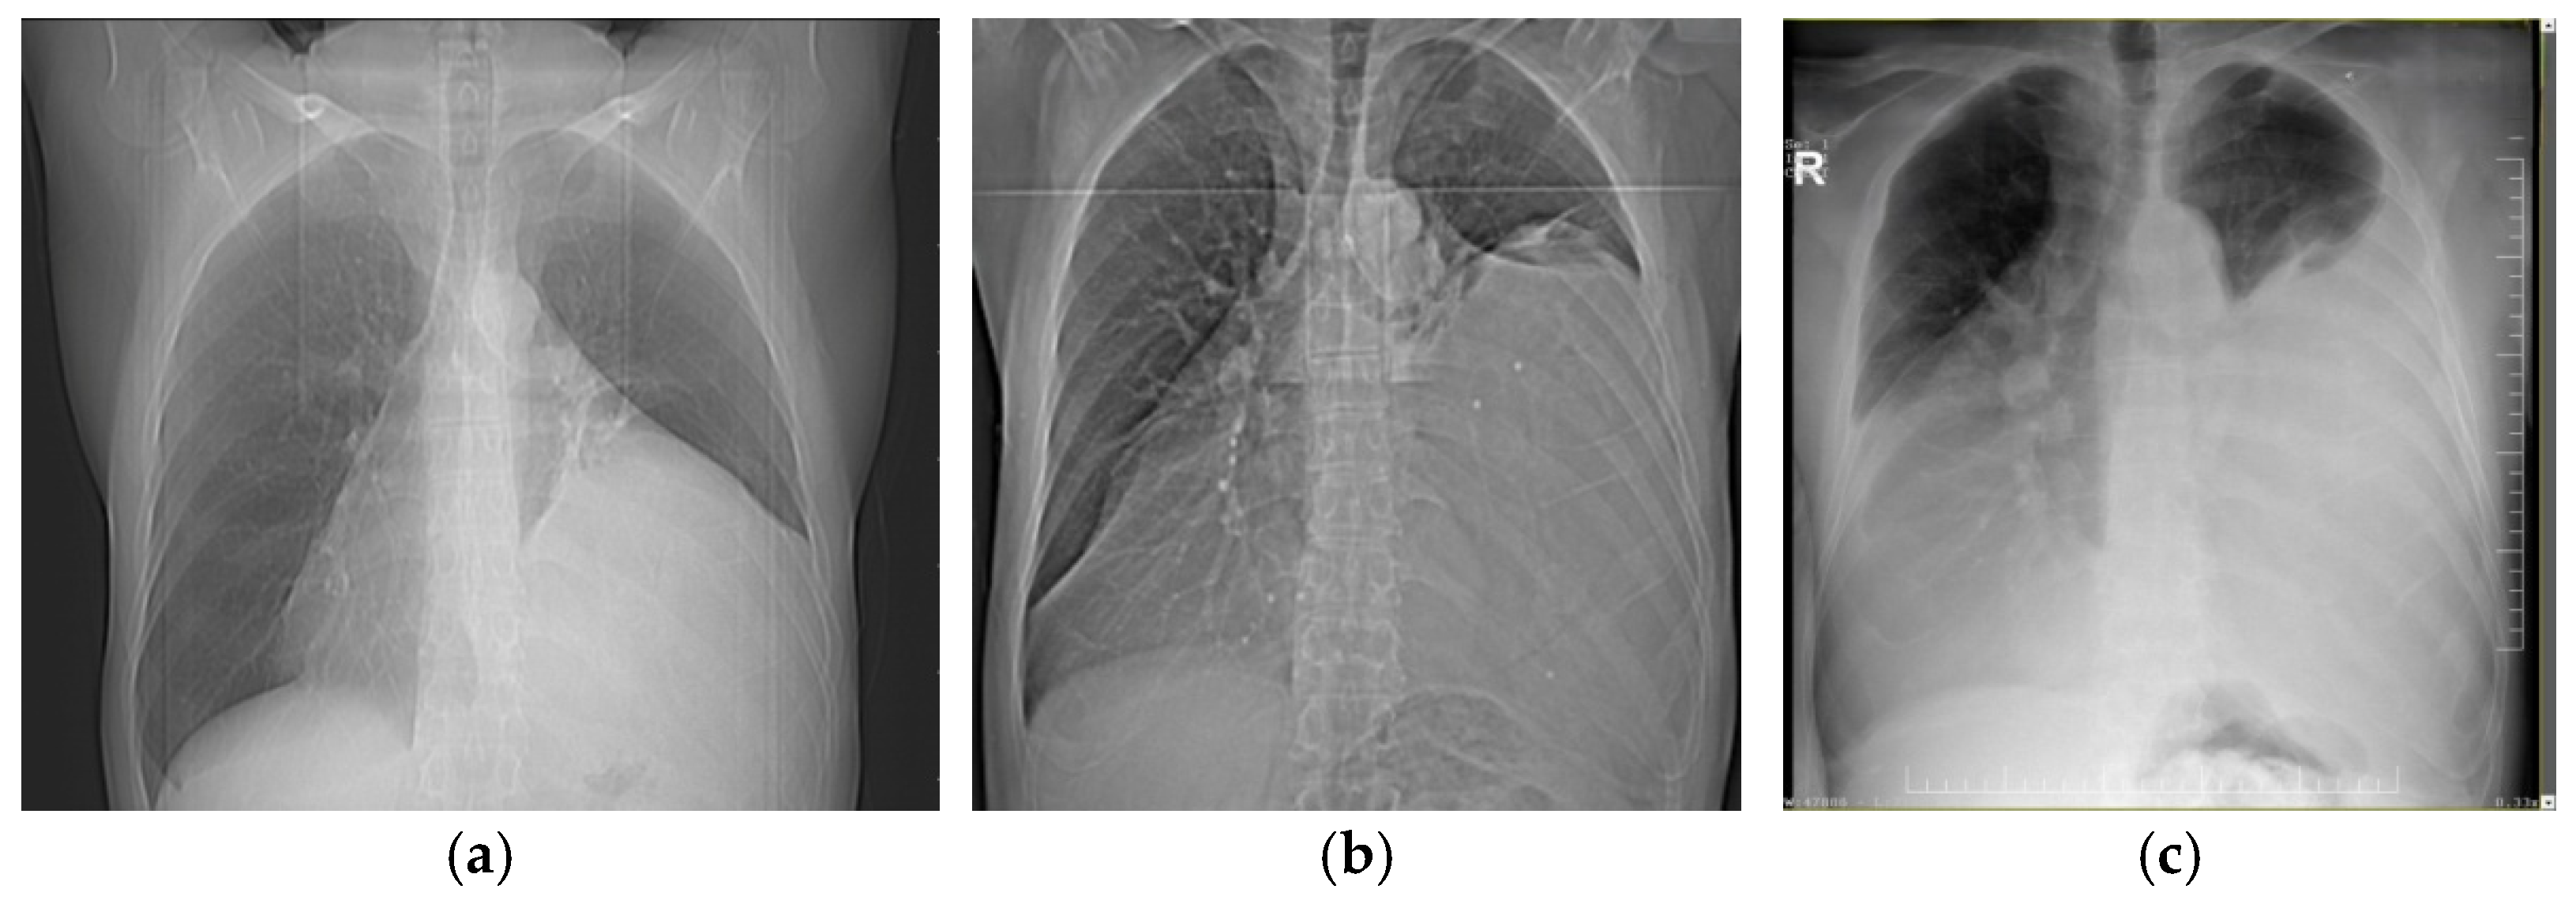

| CRC 1 (minimal compression) |

|

| CRC 2 (moderate compression) |

| CRC 3 (“giant mediastinal tumor”) | |

| CRC 3A |

| CRC 3B |